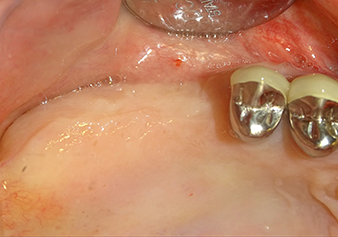

Following an intermediate check (Fig. 4) a further preparation step was performed (Fig. 5). Afterwards, the hydraulic Z35P instrument was used to lift the membrane to the desired position (Fig. 6 and 7). This was followed by further piezosurgical preparation of the implant bed, concluded with a rotary bur and shoulder milling cutter up to the implant diameter of 4.8 mm. Before the implant was inserted, the augmentation material (particle size approx. 0.8-1.6 mm) was introduced underneath the Schneiderian membrane (Fig. 8).

To move the augmentation material in the direction of the maxillary sinus atraumatically, the implant was inserted very slowly by hand (Fig. 9). In the process, the membrane was pushed in the cranial direction once again. After two months, the surgical site healed without irritation. Six months later, the x-ray check showed a significant increase in opacity as an indication of ossification (Fig. 10). The prosthetic restoration was carried out with a metal-ceramic crown.